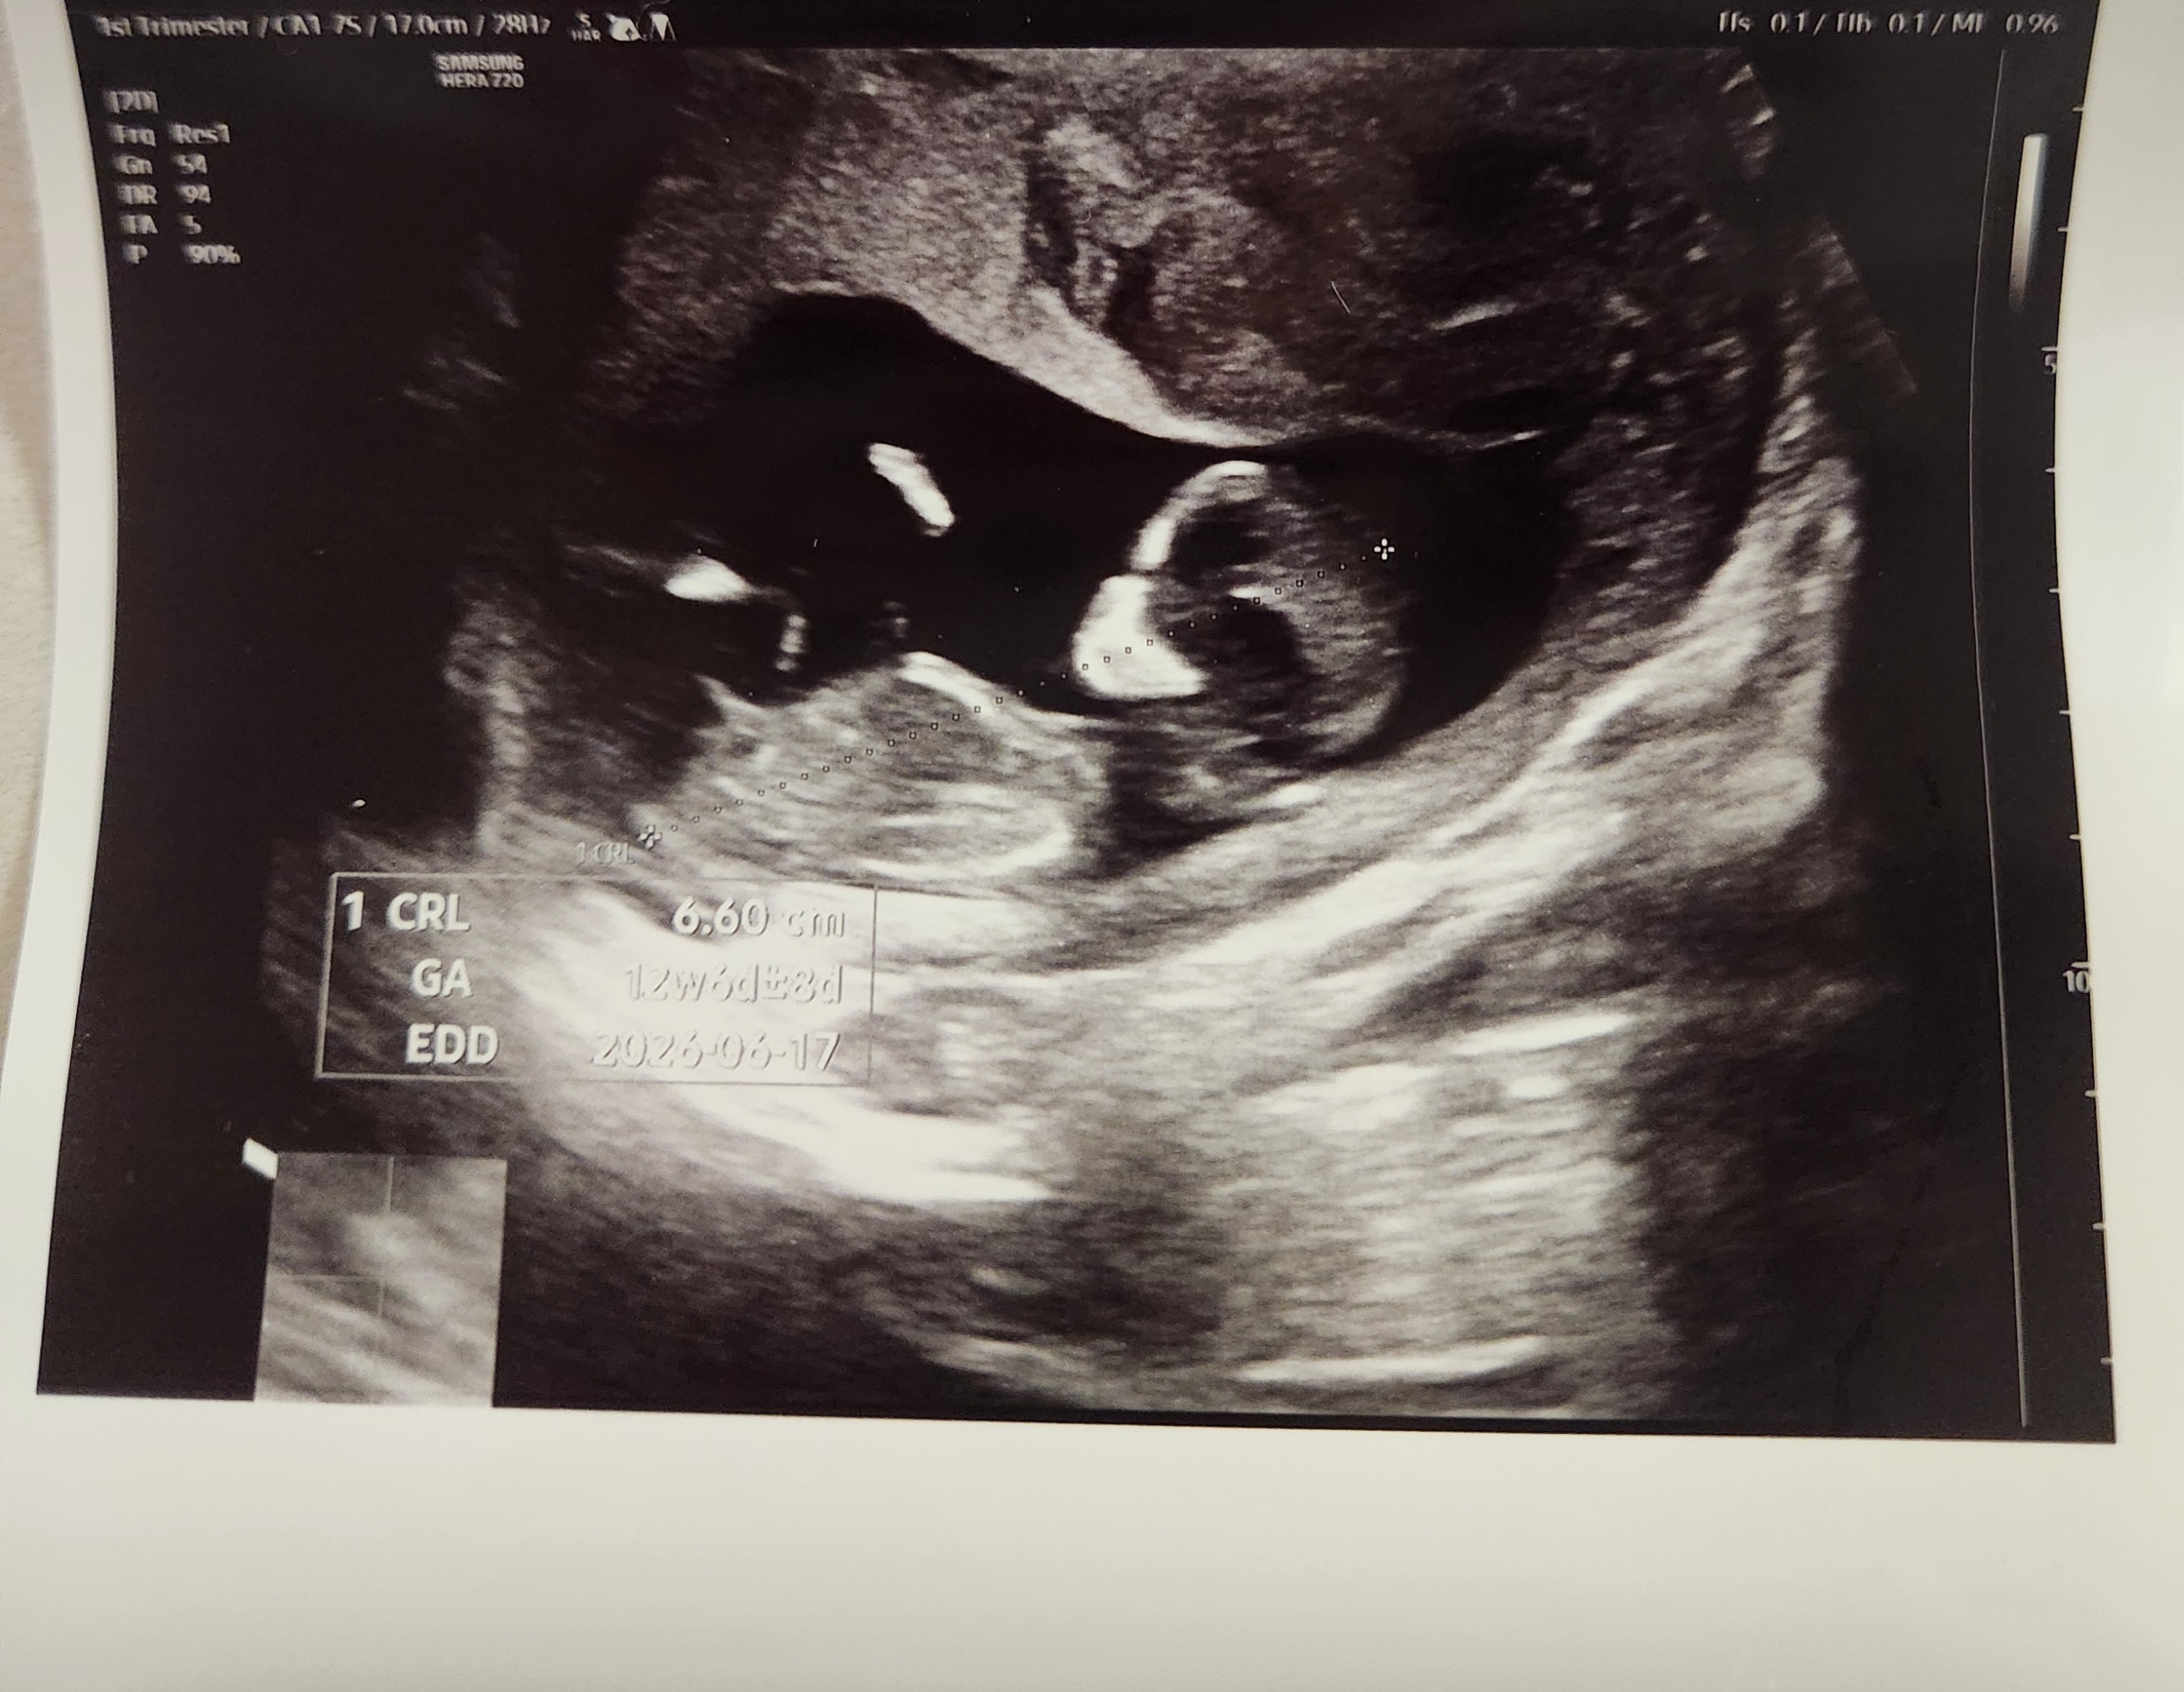

12주3일차입니다!